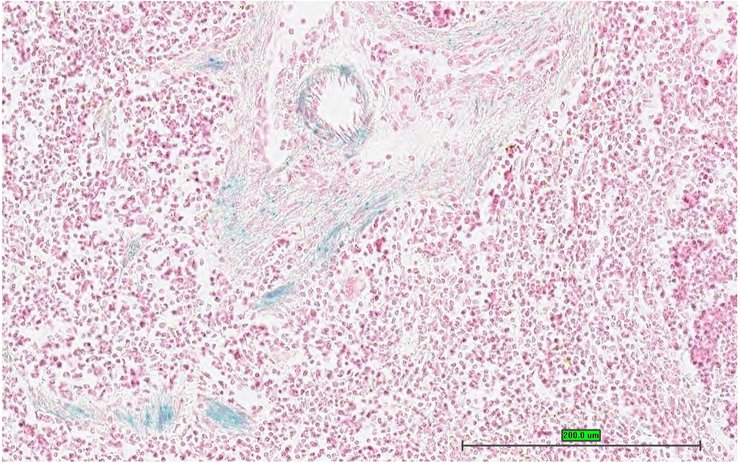

TS28: spleen Present UC Davis_1859581

Specimen UC Davis_1859582: postnatal adult; Pdk4tm1b(KOMP)Wtsi/Pdk4+ (more )

Structure Level Pattern Image Note

TS28: spleen Present UC Davis_1859582